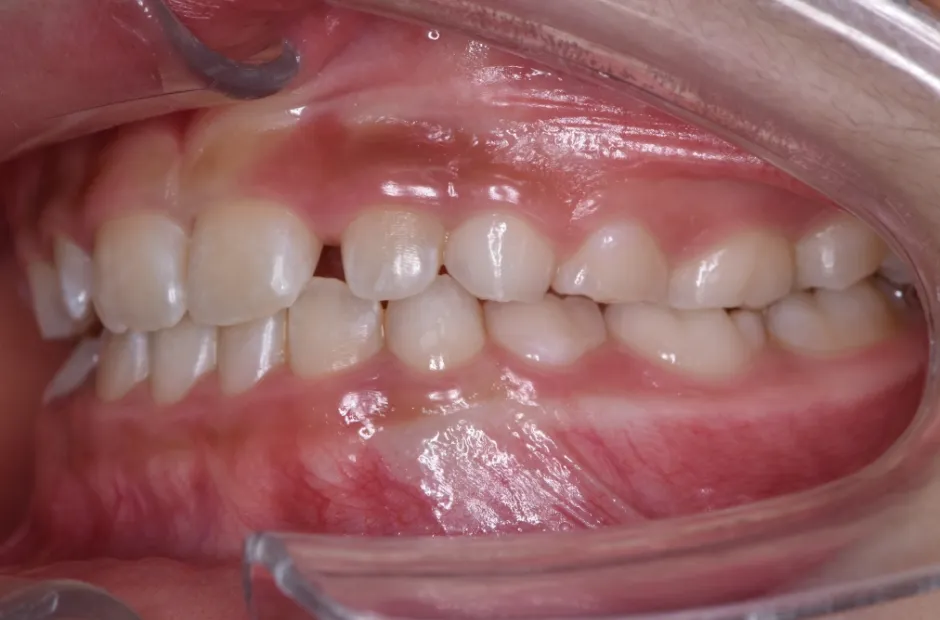

出っ歯

| 診断名・主訴 | 出っ歯 |

|---|---|

| 年齢・性別 | 16歳・男性 |

| 治療期間・回数 | 1年4か月 |

| 治療に用いた主な装置 | ブラケット |

| 抜歯部位 | 上顎4,4 |

| 治療費 | 60万円(税抜) |

| リスク・副作用 | 装置による違和感・疼痛・歯肉退縮・歯根吸収・虫歯のリスクなど |

治療前

治療後